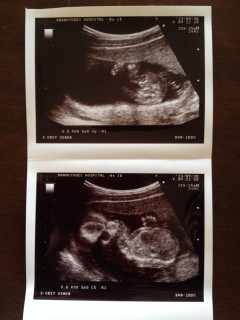

上が股の写真です。女の子の夢を見たので女の子かな~っと思っていたら,先生に(何かぶらさがってますね~)って言われました! まだはっきり確定ではないのですが,ほぼ男の子の可能性 大 !!です★ 下の写真はカメラ目線で何だか笑ってるようにも見えます★ 胎動も感じはじめ,とても楽しみです★★